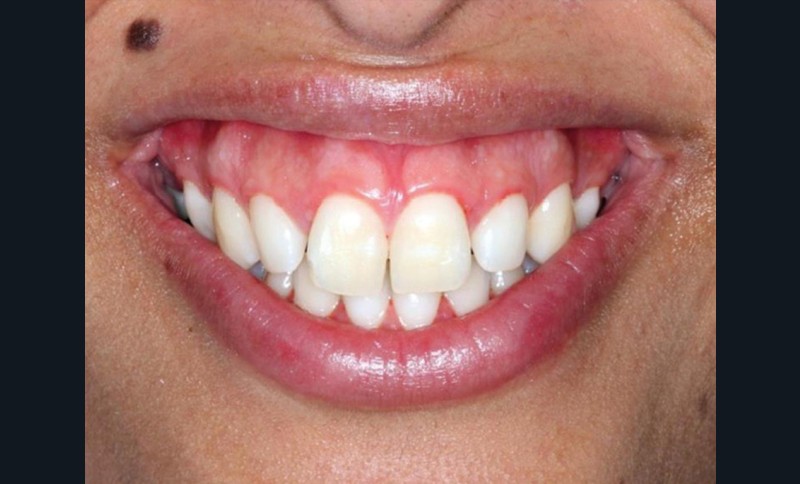

À côté de la coopération moindre qu’ils exigent, les ancrages squelettiques présentent également l’avantage de répondre à des indications très variées : correction des sourires gingivaux (Dr Skander Ellouze, fig. 3a-c), distalisation ou mésialisation molaire, supports pour les masques faciaux, mini transpalatin sur vis après expansion, ressorts de rétraction pour mettre en place les canines incluses sans léser les racines des dents adjacentes [3] (Dr Stéphane Renger, fig. 4) ou appareils d’expansion maxillaire (Dr Hans Winsauer, Dr Guido Sampersmans, fig. 5a-c)…

Le Pr Olivier Sorel insistera sur l’importance du respect des formes et des proportions anatomiques, pour éviter de voir apparaître, notamment chez les adultes, de très inesthétiques triangles noirs lors de la phase d’alignement (fig. 6a-b). Il présentera sa démarche diagnostique (évaluation de la forme des dents et de la dysharmonie dento-dentaire, fig. 7a-c) et l’intégration de la réduction amélaire proximale au plan de traitement, afin de s’assurer, en fin de traitement, la présence de papilles gingivales et donc d’un sourire harmonieux (fig. 8a-d).